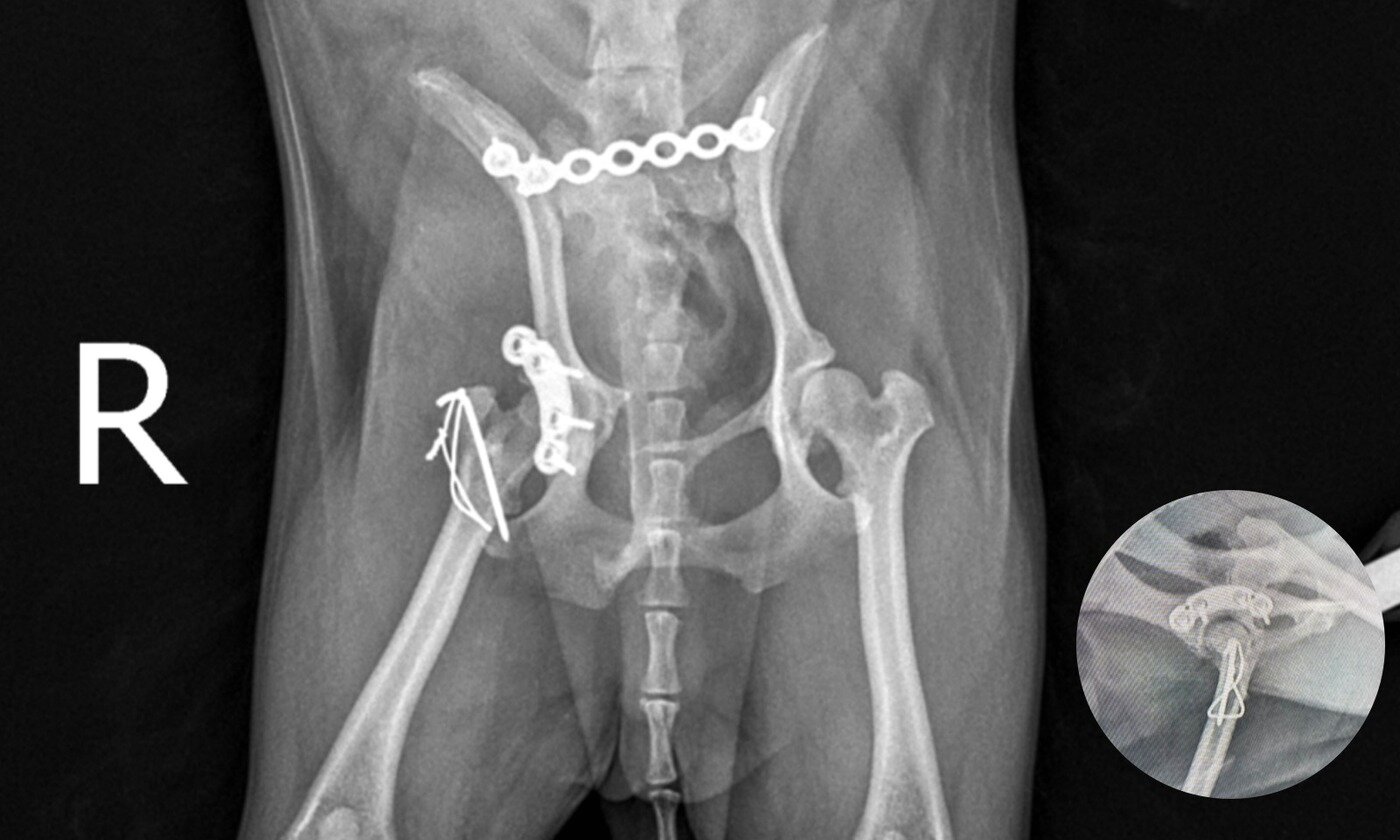

본문 이미지 - 골반 골절 수술 후 방사선 사진(예은동물의료센터 제공) ⓒ 뉴스1

골반 골절 수술 후 방사선 사진(예은동물의료센터 제공) ⓒ 뉴스1